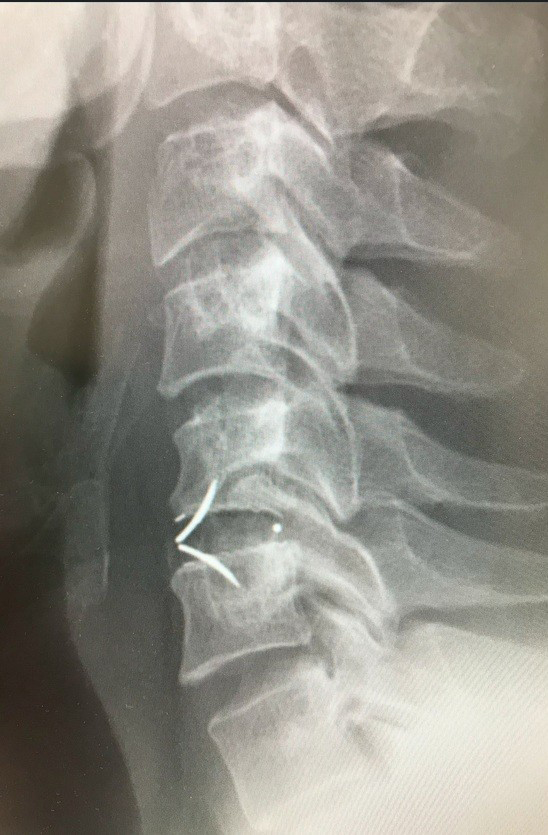

PECF(内視鏡下頚椎椎間孔拡大術)

頚椎椎間板ヘルニア、頚椎症性神経根症とPECFについて

椎間板ヘルニアというと腰椎椎間板ヘルニアが有名ですが、頚椎(くび)のせぼねにも椎間板は存在し、頚椎椎間板ヘルニアを発症することがあります。椎間板組織の一部が飛び出し神経を圧迫する病気です。そのため首から肩、腕、肩甲骨にかけて痛みやしびれが起きます。症状が強い方では力が入りにくくなることもあります。

また、頚椎症性神経根症とは骨棘(こつきょく)とよばれる加齢にともなって生じる骨の変形によって神経の通り道(椎間孔といいます)が狭くなり、神経が圧迫されてしまう病気です。

頚椎椎間板ヘルニアと同様に、首、腕などに痛みやしびれが現れます。

PECF(Percutaneous Endoscopic Cervical Foraminotomyの略称です)は、8~10㎜の小切開で患部にFESSで用いられる専用の内視鏡を挿入し、神経を圧迫の原因となっている骨、靭帯、椎間板を取り除き、椎間孔とよばれる神経が存在する通り道を広げる手術方法です。

傷が小さいため頚椎の周りの筋肉組織などへのダメージがとても少なく、術後の創部の痛みが軽減され、早期の社会復帰を果たすことが可能になります。当院では約1~2週間程度の入院期間で行っております。

病気や治療は患者様の状態によって異なりますので、すべての頚椎の疾患に対して適用できるわけではありません。外来で担当医にご相談ください。